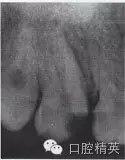

患牙根管的數(shù)目、位置以及根管的彎曲度和彎曲方向,也是影響外形制備的重要因素。為了使根管預(yù)備器械在無干擾的情況下進(jìn)入每一個根管,洞壁經(jīng)常被延長,入口的外形就隨之發(fā)生改變(圖4-2、3)。

圖4-2 洞壁被延長

A.術(shù)前X線片

B.洞壁被延長

C.根充及全冠修復(fù)